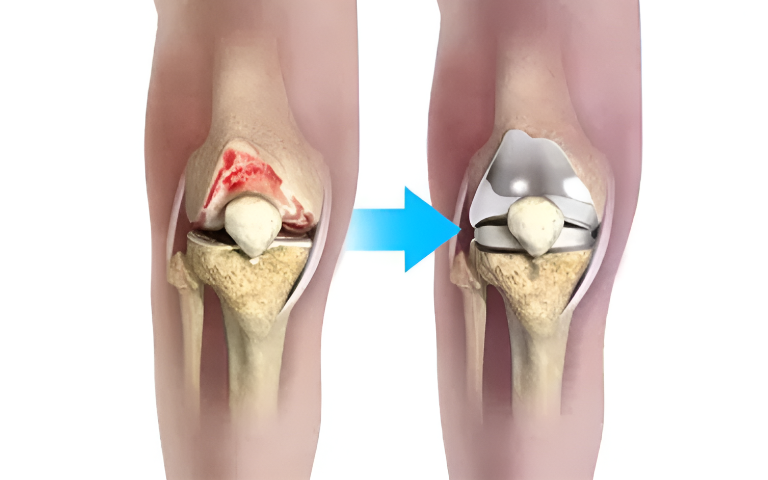

Our knee replacement procedures are performed using modern surgical techniques designed to improve alignment, stability, and implant longevity. Whether partial or total knee replacement is required, the treatment plan is tailored to the patient’s age, activity level, and joint condition. Clear pre-operative counselling, pain management protocols, and guided rehabilitation are integral to our care pathway. Patients are also counselled transparently regarding knee replacement surgery cost in Islamabad, ensuring clarity and informed decision-making throughout the process.